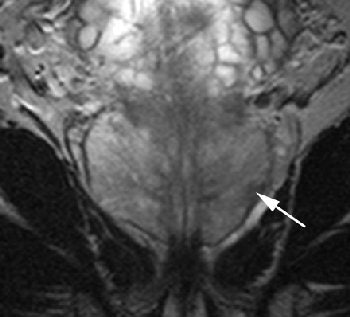

| Same patient. Coronal (C, above) T2-weighted image acquired with torso phased-array coil at 3 tesla and corresponding image acquired with combined endorectal-body phased-array coil at 1.5 tesla (D, below). |

![]() |

| Note hypointense region in peripheral zone of posterolateral aspect in A and C (arrows) and less marked hypointensity on B and D (arrows). Extracapsular extension at either field strength is not seen. Images generated with endorectal coil have better overall image quality. Histology of prostatectomy specimen yielded stage pT2c tumor. |